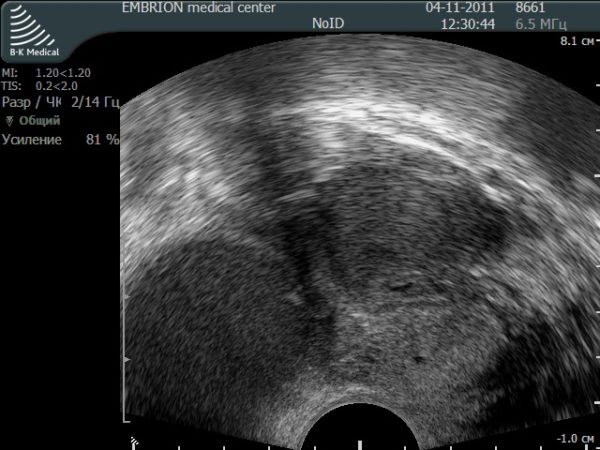

Ультразвуковые методы

Из ультразвуковых методов наиболее часто применяют ультразвуковую сонографию.

Применяют специализированные трансвагинальные датчики, которые позволяют детально оценить состояние эндометрия.

Точность указанного метода достигает 90%.

При аденомиозе отмечают увеличение размеров матки в переднезаднем размере, различная толщина стенок на всём протяжении органа.

Характерно изменение структуры по типу «пчелиных сот» — чередование плотных участков и полостей с жидкостью.

Если заболевание имеет узловую форму, то отмечают округлые плотные образования, контуры которого отличаются неровностью и отсутствием чёткости.